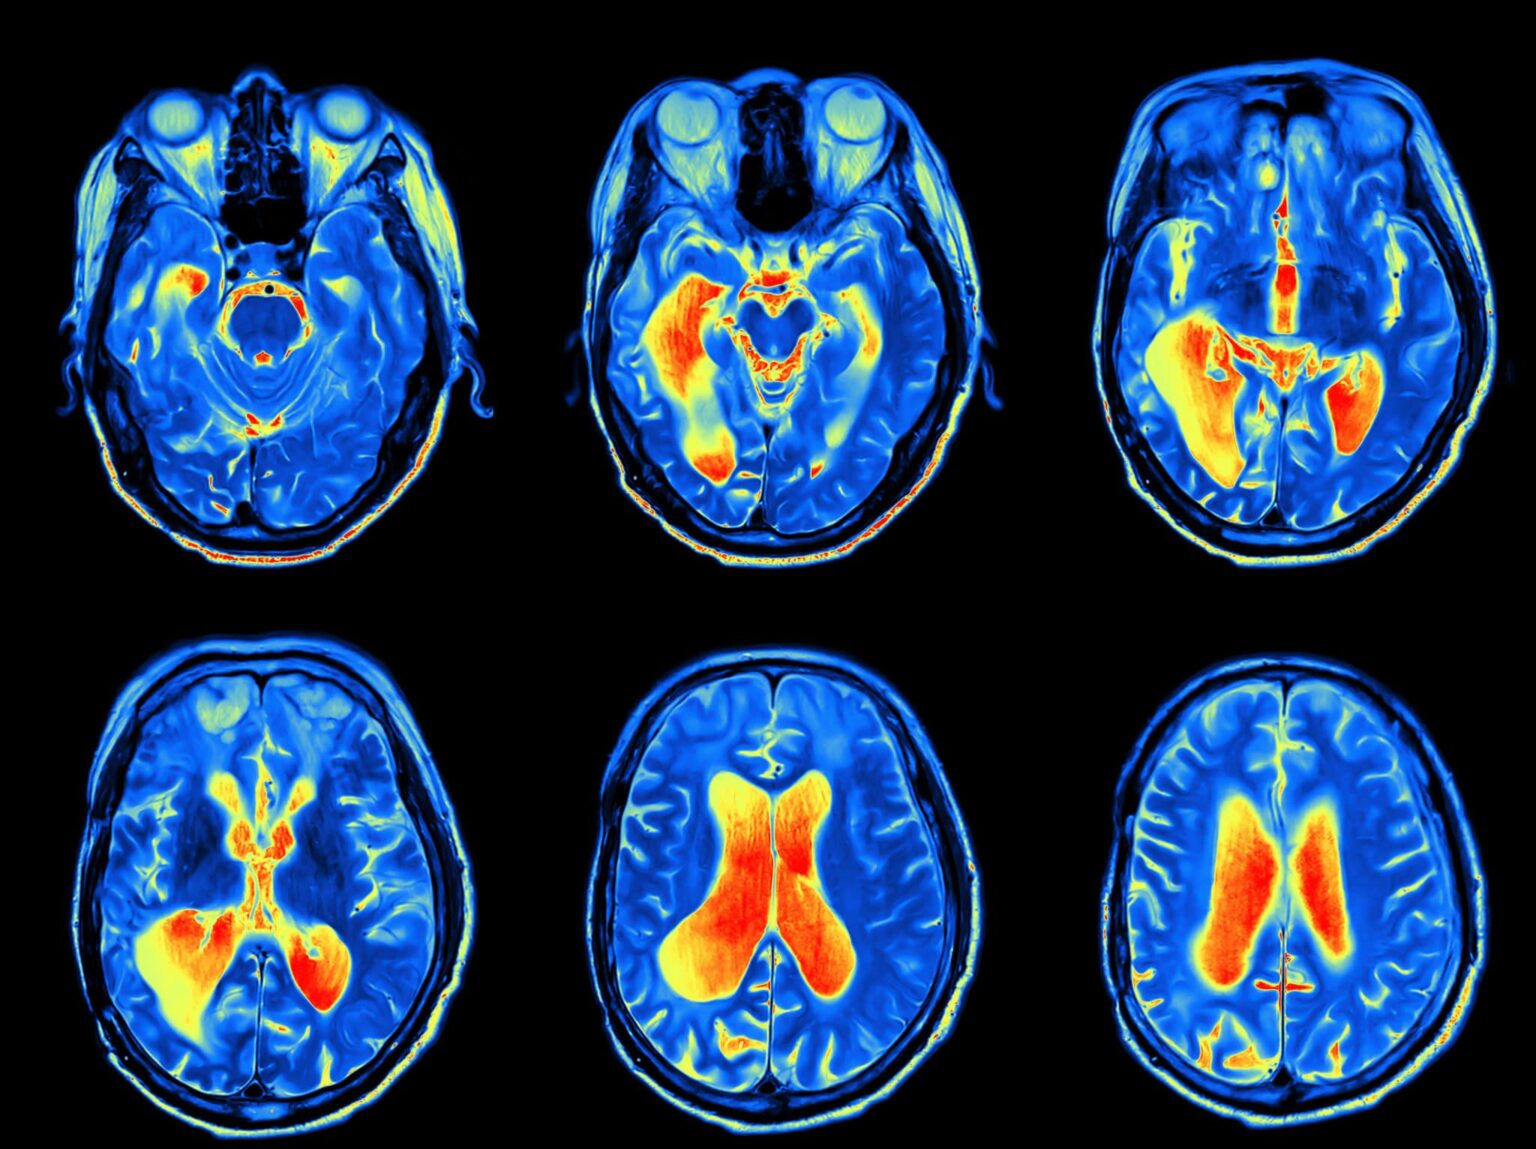

Patients with these symptoms should be evaluated, and often, imaging tests are ordered to help make the diagnosis. Once a tumor is diagnosed, a tissue biopsy is often recommended, and additional testing may be needed. Once the specific type of tumor has been determined, treatment recommendations can be made. Depending on the type of tumor, this may include surgery, radiation, and/or chemotherapy.